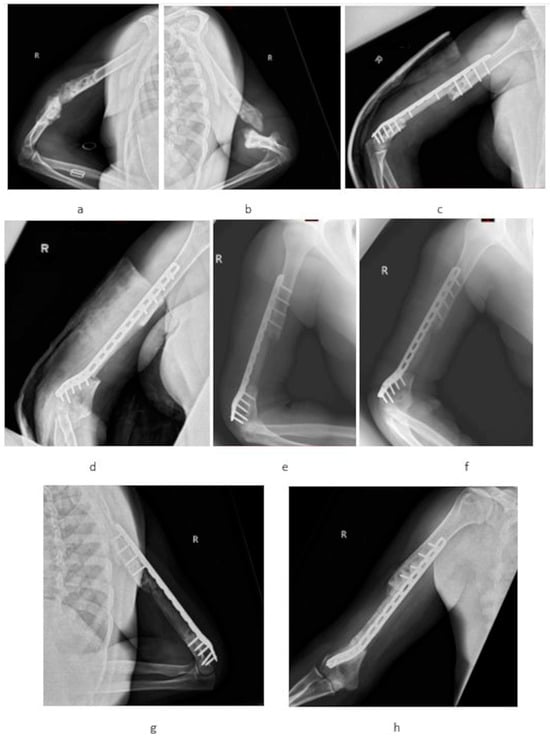

3. Results